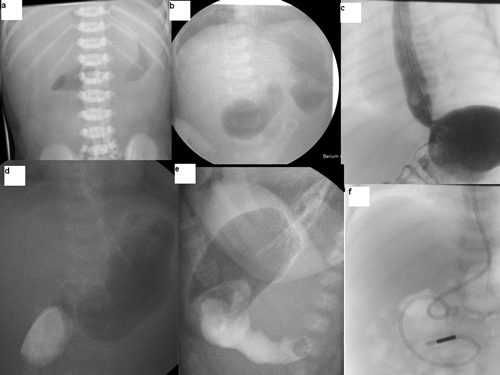

Laboratory tests showed metabolic alkalosis and acute renal failure. Capillary blood gas showed Ph 7.56, base excess -22 and HCO3 was 44 mmol/L, potassium 3 mmol/L and chloride 85 mmol/L. Plain x-ray abdomen showed gas in the stomach only (Fig. 1a). She was resuscitated, started on antibiotics and transferred to us. On arrival, baby was dehydrated but well perfused. There was visible left to right peristalsis in the epigastric region and the rest of the abdomen was scaphoid and soft. Pyloric tumour was not palpable during test feed. Complete blood count was normal. Biochemical profile showed sodium 133 mmol/L, potassium 3.6 mmol/L, urea 11.9 mmol/L, creatinine 193 mmol/L, total bilirubin 287 mmol/L with conjugated fraction being 12. Her renal functions gradually improved with adequate hydration.

Ultrasound scan of the cranium was normal. Abdominal ultrasound scan showed fluid filled distended first part of duodenum and collapsed distal bowel loops with an appearance of luminal structure like a diaphragm in the lumen of the duodenum. She underwent upper gastrointestinal contrast study and the pilot film showed double bubble appearance (Fig. 1b). There was severe gastro-oesophageal reflux up to thoracic inlet level (Fig. 1c). The stomach was hypertrophied and dilated up to first part of duodenum which was dilated (Fig. 1d). Lateral view demonstrated clear windsock deformity but it was difficult to see the rim of the attachment of the diaphragm on the duodenal wall (Fig. 1e).

Initially a small central hole was made; to see both sides of the diaphragm and the site of attachment to the duodenal wall especially to safeguard it from ampullary area in the diaphragm; followed by complete resection leaving a small thin rim close to the duodenal wall more on the medial side than the lateral aspect (Fig. 2C and 2D). The duodenal incision was closed transversely after advancing a jejunal feeding tube distally (Fig. 1f). Her post operative period was uneventful. Nasojejunal feeds were started on second postoperative day which were tolerated well. The gastro-oesophageal reflux was severe and she failed to gain weight initially and needed anti-reflux medications. She was discharged home on anti-reflux medications at 2 weeks of age. At 8-month follow-up, she was free of any reflux symptoms. The anti-reflux medications were stopped. She is now 15 months of age, asymptomatic and thriving well.

Figure 1: Plain and contrast imaging in the pre and post operative period. |